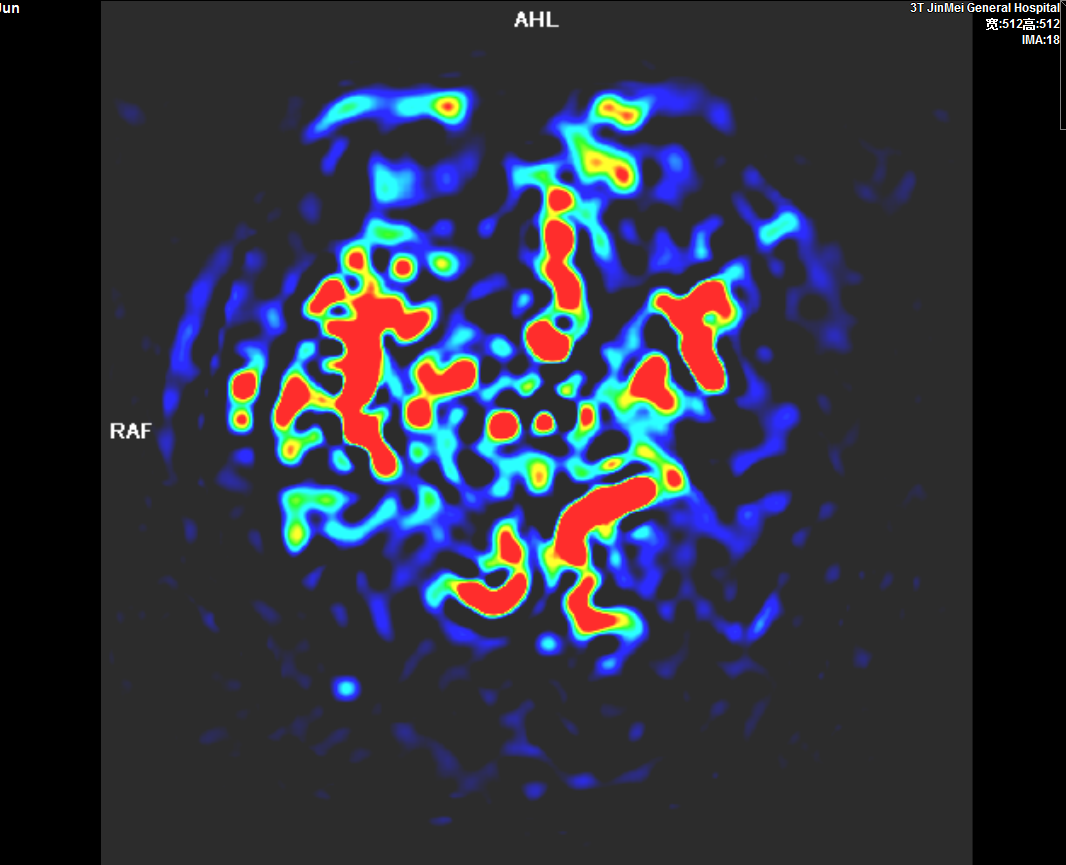

头颅灌注成像ASL

3、MRI的功能成像评价超急性期脑梗死,指导临床治疗;CTP、PWI成像评价脑缺血性病变、肿瘤性病变;CTA、MRA评价颅内外血管性病变。